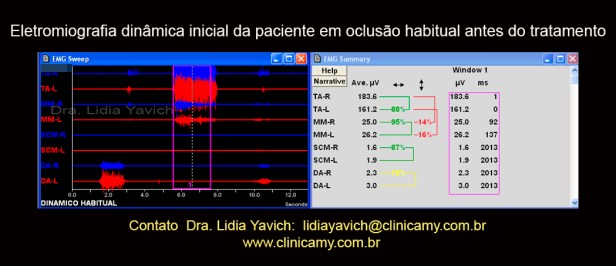

Registro eletromiográfico dinâmico em oclusão habitual da paciente antes do tratamento. Notasse a mínima ativação dos músculos masseteres direito e esquerdo na máxima intercuspidação e a alta ativação dos músculos temporais direito e esquerdo.

Registro eletromiográfico dinâmico em oclusão habitual da paciente antes do tratamento. Notasse a mínima ativação dos músculos masseteres direito e esquerdo na máxima intercuspidação e a alta ativação dos músculos temporais direito e esquerdo.

Os músculos masseteres são os músculos mais potentes do sistema estomatognático, os músculos temporais mesmo sendo músculos elevadores tem que ter uma ativação igual e preferencialmente menor que os músculos masseteres.